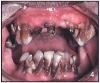

The use of MA has a pattern of damage in the mouth. There are several factors when combined that create an environment that destroys the teeth, the blood supply and supporting tissues. Figures 3 and 4 show two examples of oral destruction MA use can cause.

Figures 3 and 4 Rampant Decay – Photos courtesy of: Sharlee Shirley, RDH, MPH; Jim Cecil, DMD, MPH, University of Kentucky, School of Dentistry United States Department of Justice Meth Awareness Program